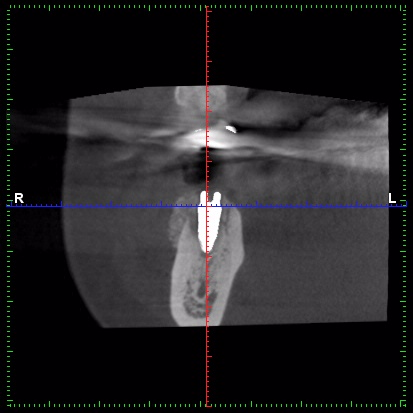

3D 列印導引式植牙

用精準3D列印手術模板讓你的植牙手術:

高精準的植牙位置、方向、角度,不只讓假牙製作可以更加完美,更重要的是避免鑽到神經或血管,使手術更安全了!